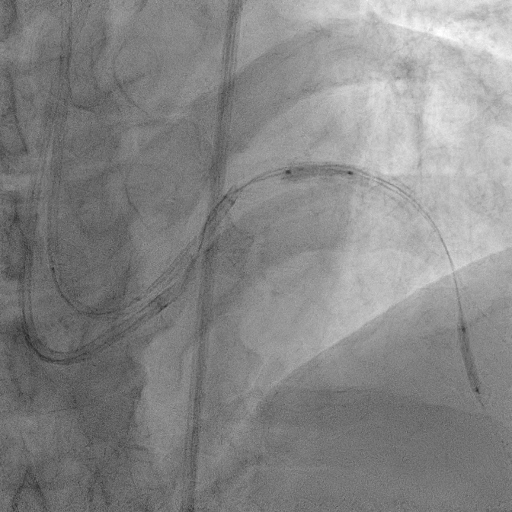

The procedure commenced with EBU 3.5/6F catheter and CTO wire with microcatheter. Managed to cross the lesion and changed to workhorse wire. Proximal LAD ISR predilated with SC balloon 2.0/15mm. CTO at mid segment predilated with same balloon. However, noted perforation at mid LAD after predilatation. We used the same balloon to tamponade the perforation and attempted to wire down distal LAD with another wire but failed. Right femoral puncture was performed and another EBU3.5/6F was used. The ping pong technique was used in which another workhorse wire to distal LAD when tamponade balloon was deflated. However, the covered stent was unable to cross the proximal LAD. Proximal segment was then predilated with NC 2.5/15mm, yet still unable to advance the covered stent. Subsequently, guide extension GuidePlus II was used and managed to advance covered stent 2.5/20mm. Tamponade balloon was then removed and covered stent deployed at perforation site. We proceeded with drug coated balloon angioplasty to proximal-mid LAD using DCB 3.5/20mm. Patient was stable and bedside echo revealed minimal pericardial effusion only